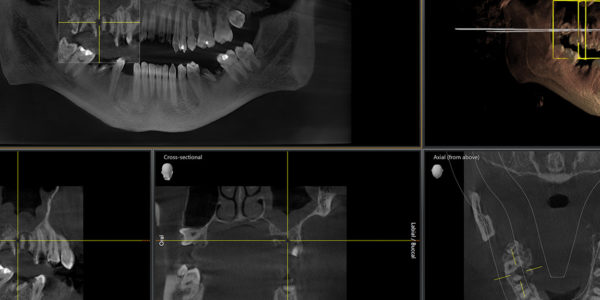

• Tomografia komputerowa szczęki żuchwy

Torbiel zatoki szczękowej22 lipca, 2025

Torbiele zatok szczękowych, choć najczęściej nie dają jednoznacznych objawów, mogą prowadzić do poważnych problemów zdrowotnych, jeśli… Dowiedz się więcej: Torbiel zatoki szczękowej